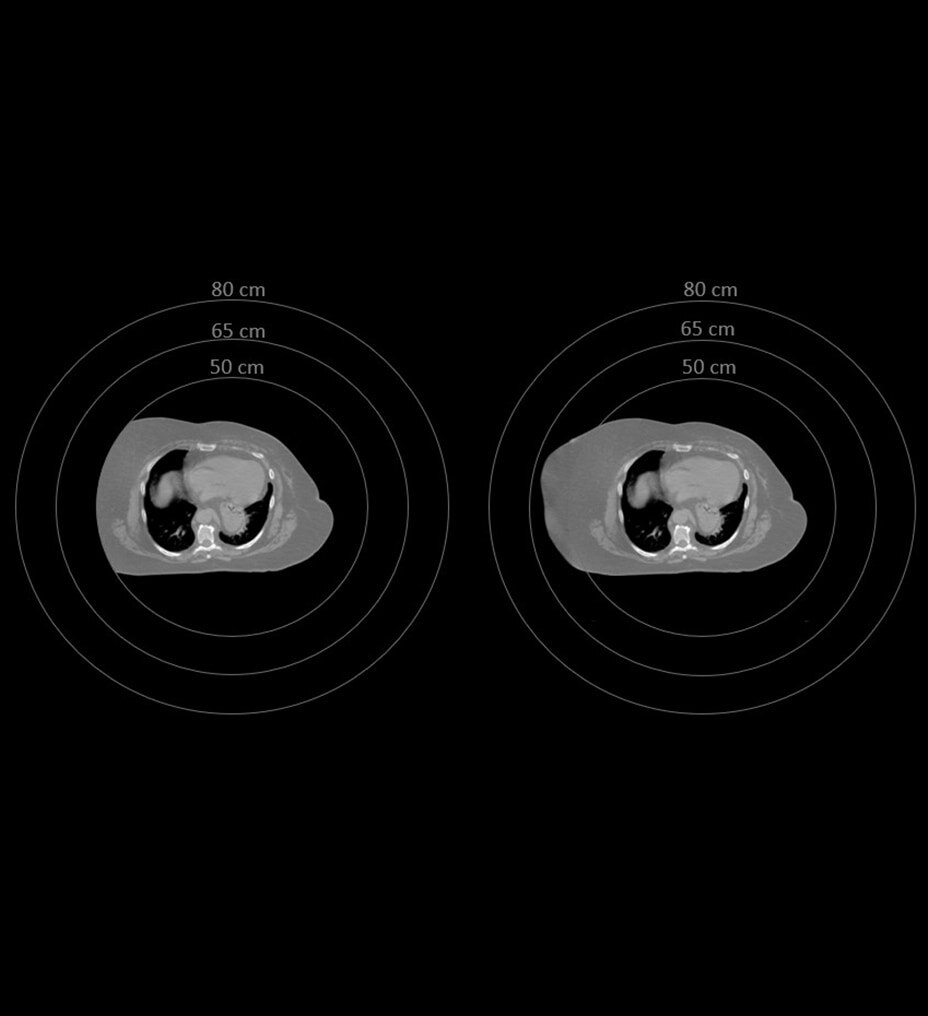

Los departamentos de radiología llevan demasiado tiempo sobrecargados de trabajo. Los tiempos de exploración de RM más rápidos liberan más espacios de turnos y crean flujos de trabajo fáciles de gestionar. Ahora, con un solo ajuste, las configuraciones de la exploración pueden simplificarse. De este modo, se pueden ampliar las capacidades de todos los usuarios. Sonic DL™ está disponible tanto para sistemas 1,5 T y 3 T nuevos como antiguos.

Los departamentos de radiología llevan demasiado tiempo sobrecargados de trabajo. Los tiempos de exploración de RM más rápidos liberan más espacios de exploración y crean flujos de trabajo fáciles de gestionar. Ahora, con una sola palanca, las configuraciones de la exploración pueden simplificarse. De este modo, se pueden ampliar las capacidades de todos los usuarios. Sonic DL™ está disponible tanto para sistemas 1,5 T y 3 T nuevos como antiguos.